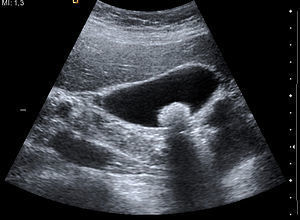

Safra yolları karaciğer içerisinde ince kanallar şeklinde başlar. Daha sonra bu kanallar birleşerek karaciğerin sağ ve sol lobunda iki ana kanal halinde gelir. Bu iki kanal karaciğer çıkışında birleşir. Daha sonra bu kanala safra kesesi kanalı da eklenerek koledok kanalı oluşur ve on iki parmak bağırsağına açılır. Bu kanal sistemi içerisinden gelişen her hangi bir kitle, kanallarda genişlemeler yada kistler ultrason inceleme ile saptanabilir. Safra kesesi hastalıkları günümüzde sık görülmektedir. Bu hastalıklardan en sık olanları safra kesesi taşları ve safra kesesi iltihabıdır. Her iki durumda ultrasonda kolaylıkla görülüp bir an önce tedaviye başlanabilir.